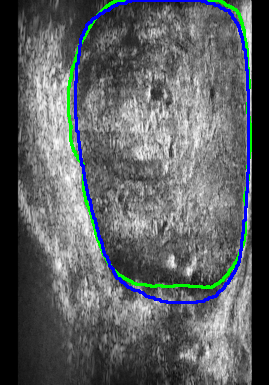

Figure 4 presents the performance evaluation of three loss functions—Adaptive Focal Loss, AG-BCE Loss, and PyTorch Focal Loss—on three test images. Each row in the figure corresponds to the segmentation results of one loss function, while the columns represent the respective test images. A legend at the top provides the color coding for the ground truth and the outputs of the three loss functions, allowing for a direct visual comparison of their performance.

The visual analysis of segmentation results, illustrated in Figure 5, demonstrates that Adaptive Focal Loss consistently achieves more accurate segmentation, particularly in regions with low contrast, high noise, or complex anatomical variations, closely aligning with the ground truth.

1.

Test Image 04: The Adaptive Focal Loss function excelled in capturing the prostate boundary, especially in the lower-left region obscured by speckle noise. By comparison, AG-BCE and PyTorch Focal Loss exhibited significant deviations, notably under-segmenting the prostate and failing to depict the boundary accurately.

-

2.

Test Image 11: The Adaptive Focal Loss function demonstrated superior performance in the upper-right region, where the prostate boundary was subtly defined against surrounding tissue. AG-BCE failed to capture finer details, producing a less smooth boundary and shifting it inward, while PyTorch Focal Loss over-segmented, extending beyond the prostate.

3.

Test Image 14: Despite complex artifacts in the lower region, Adaptive Focal Loss maintained a boundary closely resembling the ground truth. AG-BCE exhibited minor mismatches, particularly in the lower-right corner, while PyTorch Focal Loss underperformed, displaying over-segmentation and boundary deviations.